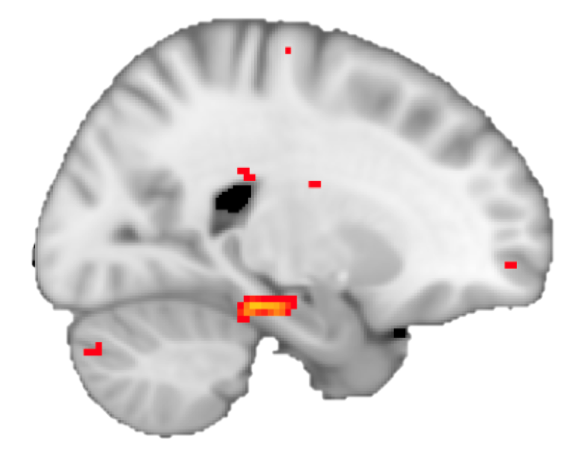

Very happy to see our paper out in @NeuroCellPress! We show that the brain abstracts and generalises the structure of reinforcement learning tasks. Link to the paper: https://t.co/Mpu4jJVtdr

This suggests that participants formed and used a map for generalization! And indeed, using fMRI adaptation we found a representation of the spatial map in the hippocampus. However, not only spatial relationships between monsters were represented in the hippocampus!